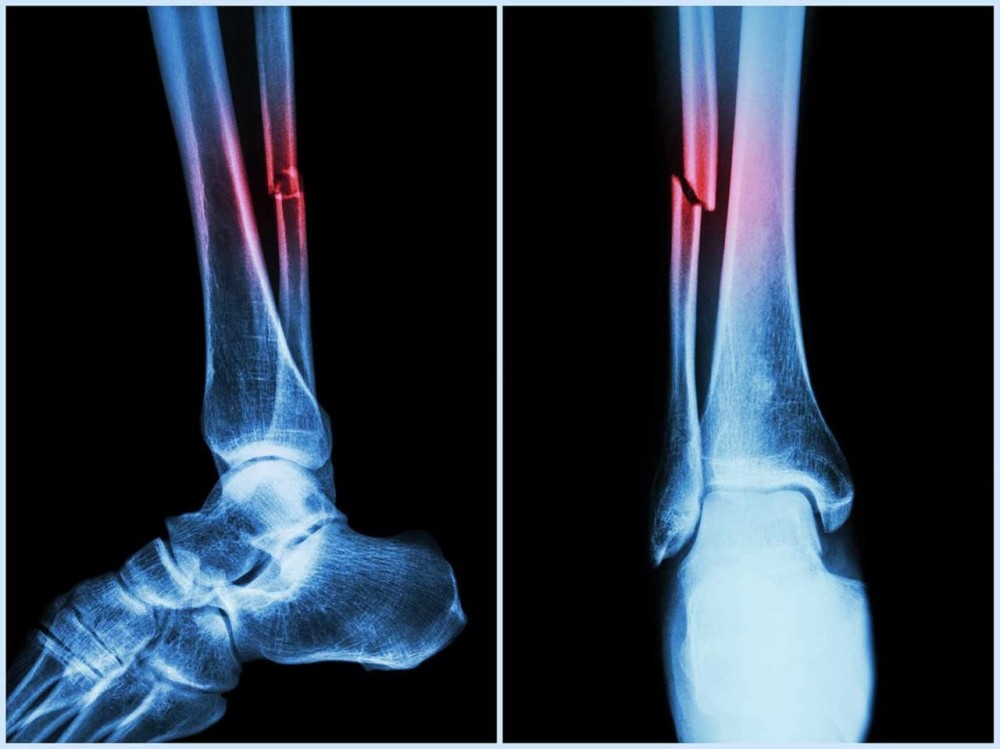

Further research by ECU's Marc Sim revealed that AAC is not only a cardiovascular risk indicator but also a strong predictor of falls and fractures. In fact, AAC outperformed traditional fall risk factors like bone mineral density and past fall history.

"The higher the calcification in your arteries, the higher the risk of falls and fractures," Sim said, adding clinicians typically overlook vascular health in fall assessments, and this algorithm changes that.

Sim said that the new machine algorithm, when applied to bone density scans, could give clinicians more information about the vascular health of patients, which is an under-recognised risk factor for falls and fractures.